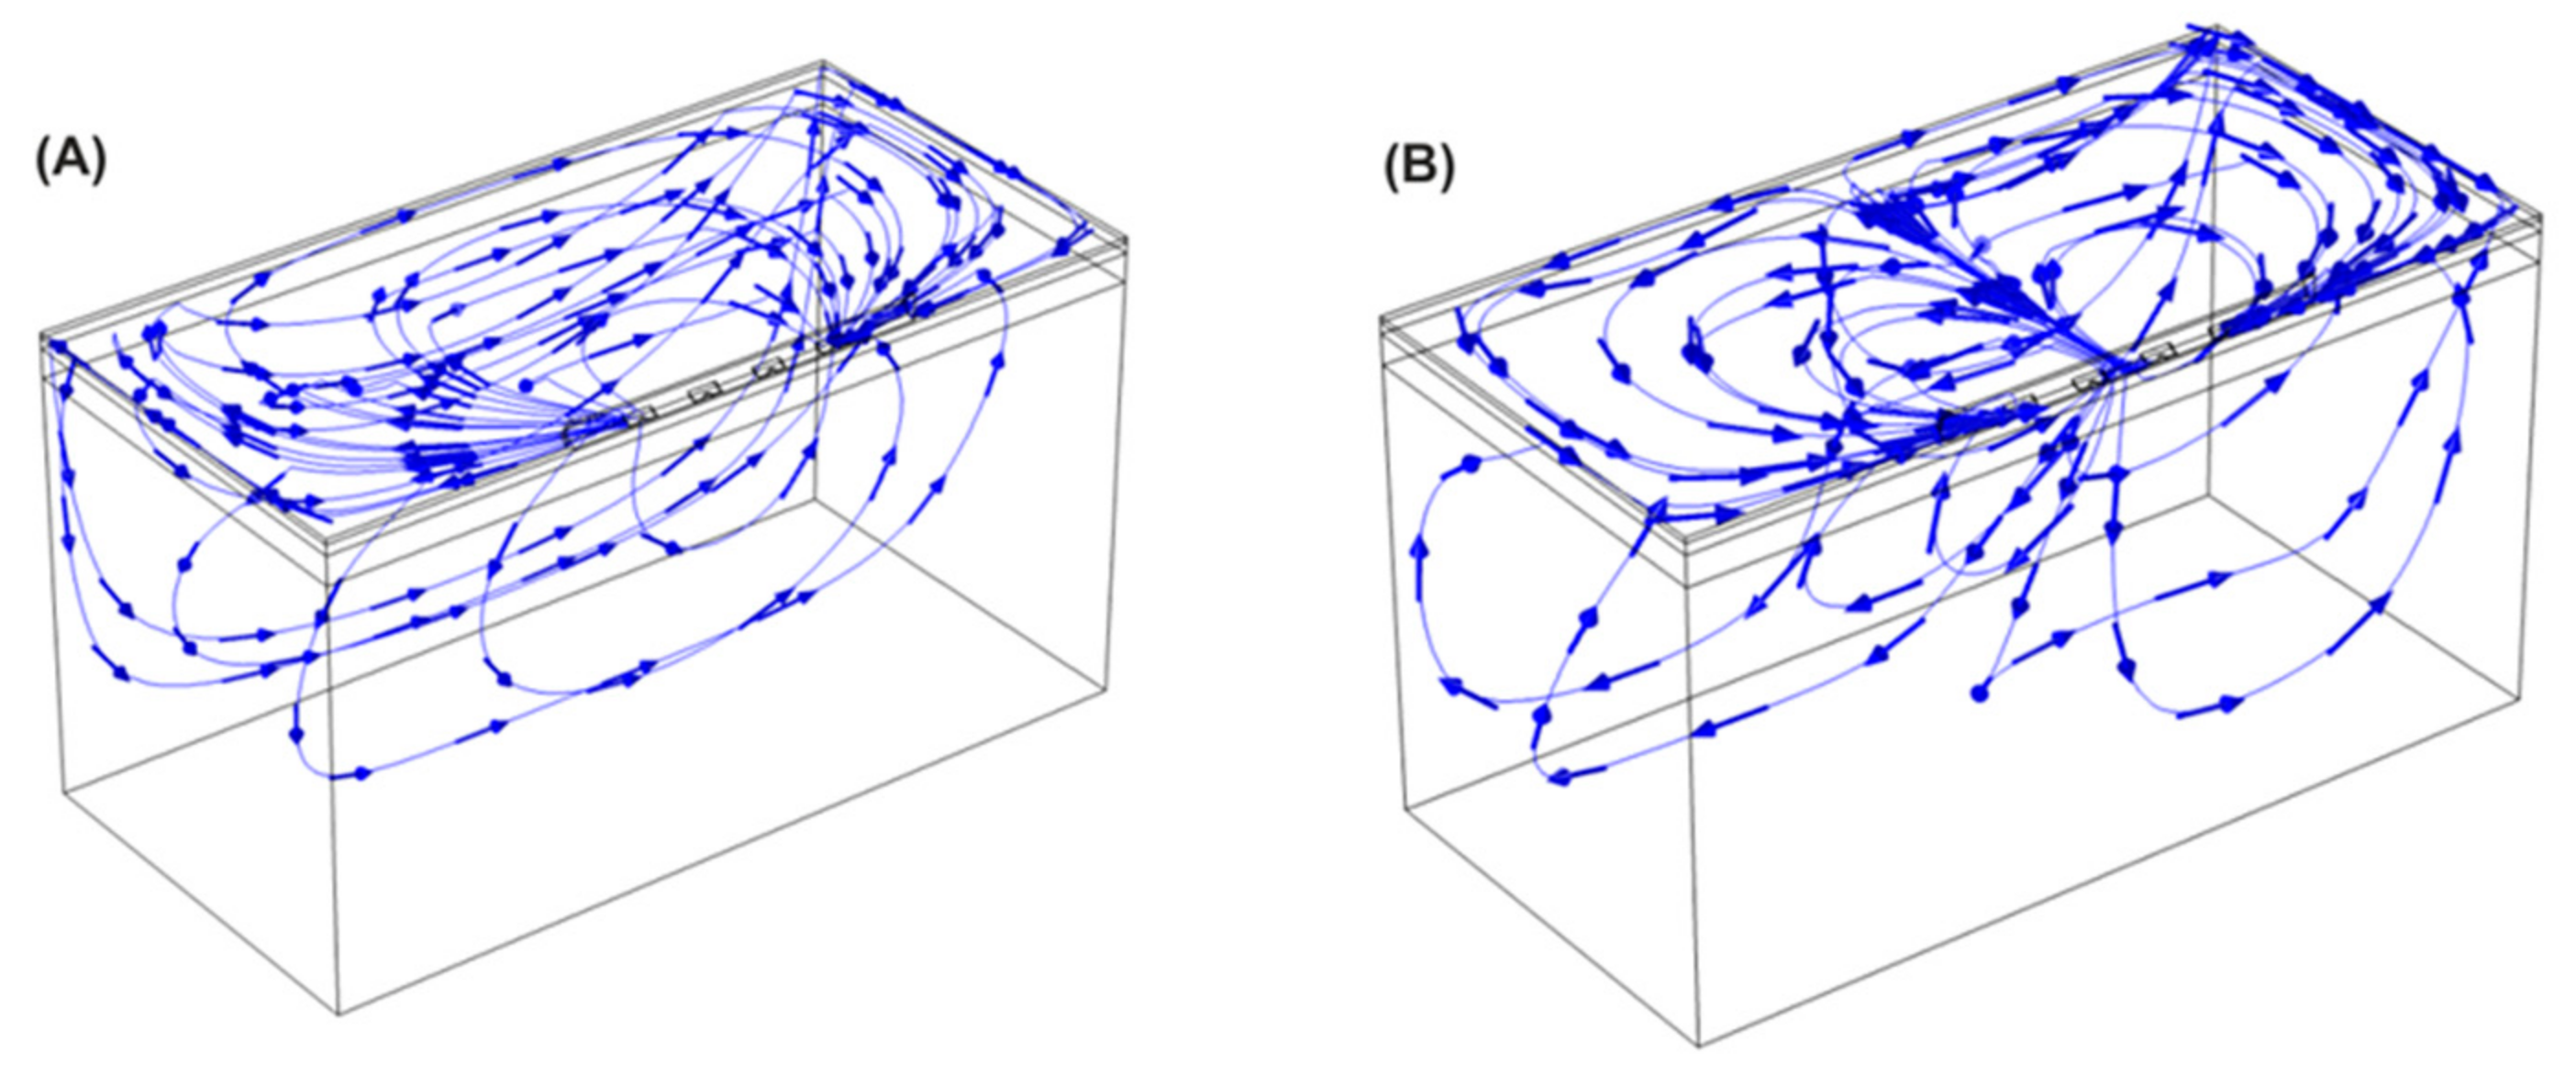

2.2. Electric Field Modeling

3.1. Electric Field Models